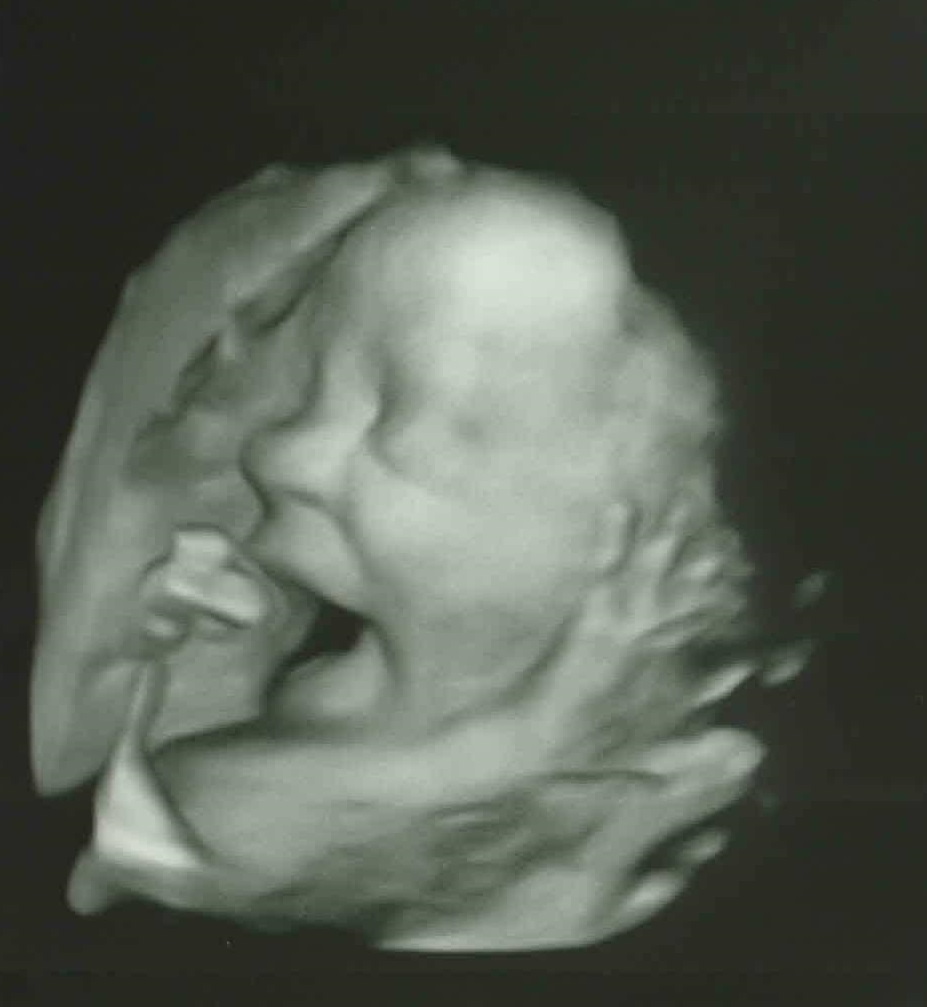

| Above: a 28-week-old baby |